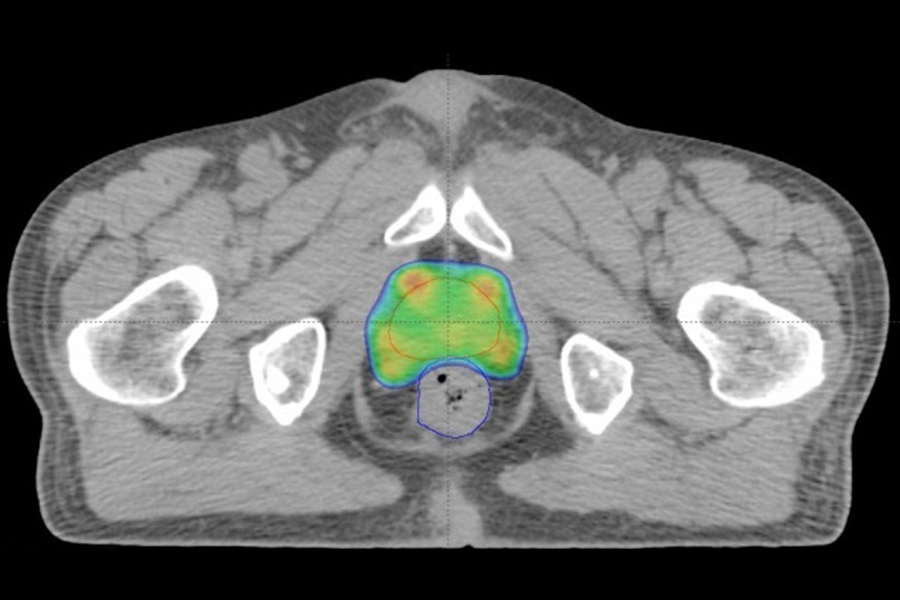

強度変調放射線治療:IMRT(Intensity-Modulated Radiation Therapy)

複雑な腫瘍形状に合わせて線量分布を形成する治療法です。腫瘍へ当たる放射線の線量を保ったまま、近接する正常臓器への線量を減らすことが出来るため、副作用に配慮した治療が可能です。様々な腫瘍に対して用いられますが、特に前立腺癌治療や頭頚部癌治療などにおいてはその有用性が広く知られています。